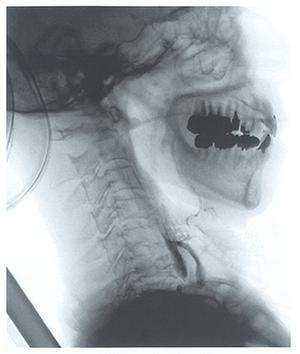

4

第53回 午後

|

作業療法士実地問題

嚥下造影検査の嚥下反射終了後の静止画像を示す。咳反射はない。認める所見はどれか。

1

誤 嚥

2

声門閉鎖

3

頸椎前弯

口腔内残留

5

食道入口部開大